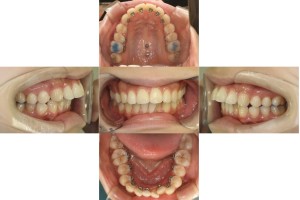

リンガル矯正なので上下裏側に装置を付けさせて頂きました。

上顎に小さなネジ(アンカースクリュー)を埋入し、歯を引っ張る土台(固定源)にして効率的に動かしていきます。

上顎両側4番目の歯を抜歯をして、口元を下げていきます。